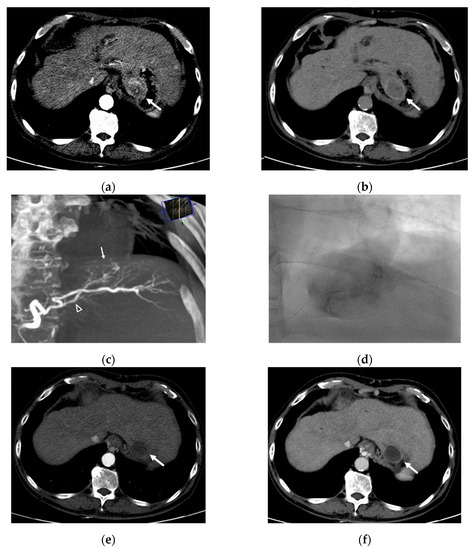

All procedures were performed by one interventional radiologist with 10 years of experience. After common femoral artery cannulation under local anesthesia, diagnostic angiography of the superior mesenteric artery and celiac artery (including cone-beam computed tomography [CT]) was performed with a 5-Fr catheter (Yashiro; Terumo, Tokyo, Japan) to outline the anatomy and delineate the tumors. A 2.0-Fr coaxial microcatheter (Progreat, Terumo) was then used to catheterize the feeding vessels supplying the HCC. The microcatheter was placed as distally as possible into the vessel supplying the tumor, and the tip of the catheter was advanced into the hepatic artery and the feeding branch if the size, location, and blood supply were allowed. Under fluoroscopy, each feeding vessel to the tumor was embolized by slow injection of an iodinated contrast material mixed with either 70–150 μm or 100–300 μm DC beads (Biocompatibles UK Ltd., Farnham, UK, BTG) impregnated with 50 mg of doxorubicin in each vial. The doxorubicin dose was calculated according to the infused microsphere volume. For example, when half of one vial of DEB was infused, the used doxorubicin dose was calculated as 25 mg. Termination of injection was indicated by stagnant flow in the feeding hepatic arteries of the tumor. If the embolization endpoint was not achieved after injection of the scheduled volume of loaded beads, polyvinyl alcohol (PVA) particles or gelatin sponge particles were administered until near stasis of the target lesion had been reached. A representative case is shown in Figure 2.

Figure 2.

A 61 year-old man with HCC. (a) Arterial phase of dynamic CT shows a hypervascular mass measuring 4.1cm in diameter in segment 2 (arrow). (b) Delayed phase image from the same study shows classic tumor washout (arrow). (c) Cone-beam CT angiography shows a tumor blush (arrow) and precisely delineates single tumor feeder (arrowhead). (d) After selection of tumor feeder using microcatheter, DC Bead (70–150 µm) loaded with doxorubicin/nonionic contrast suspension is slowly injected. (e,f) Arterial and delayed-phase CT scan 3 months later shows no enhancement in the tumor, indicating complete response.